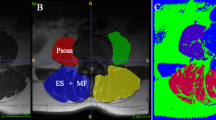

Axial T2-weighted MRI were obtained at the levels of the 3–4 and 4–5 lumbar intervertebral discs using a 1.5 T GE Signa HDxt (Milwaukee, WI, USA) with a phased-array surface coil. CSA of both sides of the paraspinal and psoas muscles were measured with Agfa Impax workstation software (Mortsel, Belgium) by tracing the borders of these muscles and were expressed as cm2. Each muscle structure was circumscribed by two well-experienced radiologists (both specialized to musculoskeletal radiology) and the average value was calculated from these measures.

It has been found out that the borders between the multifidus and the erector spinae muscles (iliocostalis lumborum and longissimus thoracis pars lumborum) are often difficult to distinguish [22]. Therefore, the multifidus and erector spinae muscles were measured including the non-muscular tissue between them, together as one muscle mass, and considered as the paraspinal muscles. L3-L4 and L4-L5 were selected for the analysis because both of these levels have been used in previous studies [13, 22] and because CSA of the paraspinal muscles has previously been found to be the largest overall at the L3-L4 level [22].

In addition to the CSA measures, a qualitative muscle composition measurement was conducted by two well-experienced musculoskeletal radiologists. The atrophy of muscle was rated qualitatively for the paraspinal muscles and psoas muscles at the L3–L4 and L4-L5 levels for all subjects based on visual evaluation using a 3-point visual scale (0 = significant muscle atrophy; 1 = minor deposits of non-muscle tissue (e.g. fat), atrophy 2 = normal muscle, no apparent non-muscle tissue). The average value was calculated from these measures. The MRI measurements of muscle morphology and CSA offer valid assessment of muscularity [24], as compared to muscle function tests that may be influenced by such factors as pain and motivation.